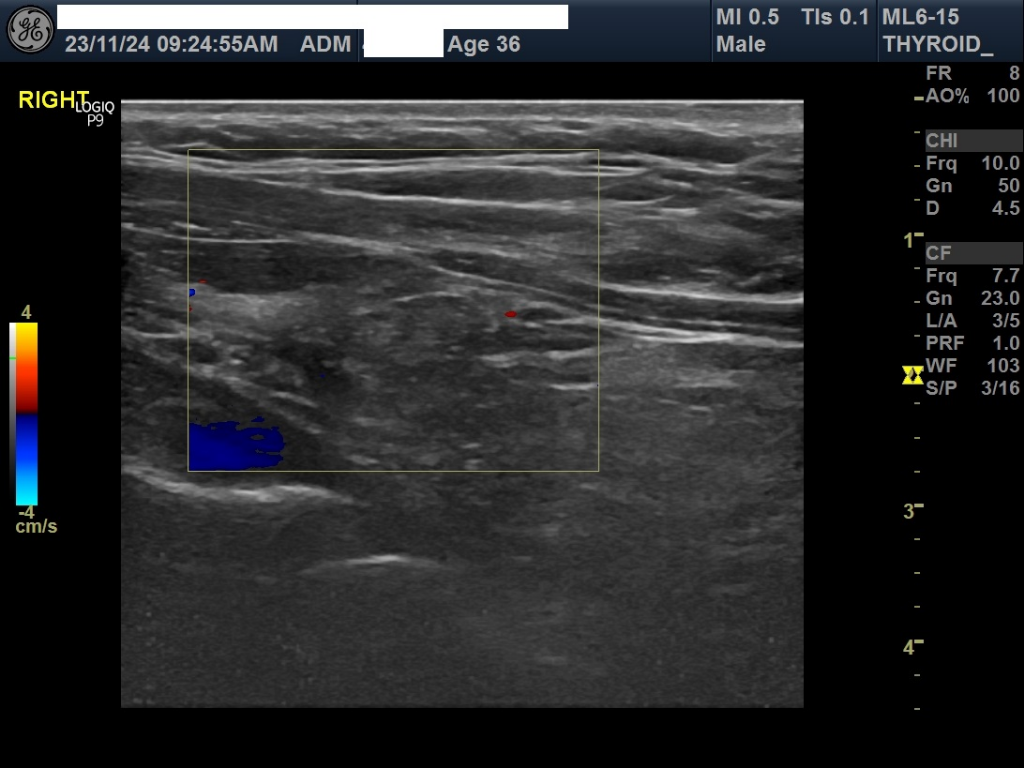

갑상선 결절이 발견되어 걱정스러우시지요. 부갑상선보다는 갑상선 내부 결절로 보입니다. 조직검사가 필요할지에 대해 갑상선 외과를 방문해보셔야 하겠습니다. 건강검진 결과를 굳이 기다릴 필요는 없으니 시간내서 방문해보시기 바랍니다.

1.18cm 크기의 결절은 상대적으로 크기가 큰편은 아닙니다. 갑상선 결절의 암 여부를 결정하는 것은 크기만으로는 불가능하며, 초음파의 세부적인 소견, 환자의 개인적인 위험 요인, 그리고 필요한 경우 세침 흡인 생검(FNA) 등 추가 검사를 통해 평가됩니다.

일반적으로, 갑상선 결절의 대부분은 즉시 긴급한 조치가 필요하지 않으니 응급으로 검사를 해야 할 이유는 없을 것으로 사료되며 혈액검사결과 소견과 함께 평가르 받으시는 것이 좋겠습니다.